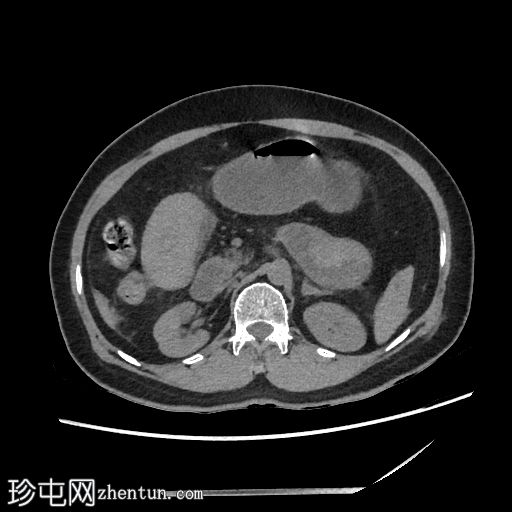

矢状位增强扫描

动脉期

空肠(长段,60 cm)肠壁弥漫性节段性增厚。肠壁呈高密度影,平扫CT值约为56 HU,并可见强化。

可见肠系膜水肿和血管充血,以及少量腹水。

肠系膜上动脉和静脉通畅,未见血栓。

影像学表现最提示黏膜下出血。